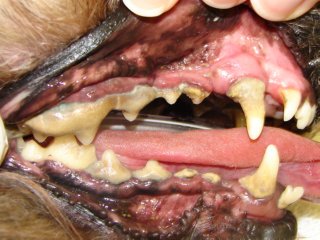

In stage IV (severe periodontitis) there is severe gum recession, bone loss and root exposure. The periodontal supporting structures are almost entirely destroyed and the teeth are mobile. Bacteria may be spreading throughout the entire body via the bloodstream and may damage the kidneys, liver and heart.

While periodontal disease is irreversible, treatment at any point in the disease process will stop or slow this progression. Without treatment, the end stage of this disease is tooth loss; however the disease has likely caused problems well before this. Bacteria from infected gums might gain access to the systemic circulation. Consequences of bacteria circulating in the main blood stream include kidney infections, liver abscesses, infectious arthritis, and birth problem in puppies. These bacteria may also become attached to heart valves and cause endocarditis which results in an intermittent infection and strokes. Clinical signs of gingivitis are swelling, a gingival color change from pink to red, bleeding gums, significant tartar, and bad breath. Clinical signs of periodontitis include the above plus gum recession, difficulty eating, and increased tooth mobility.